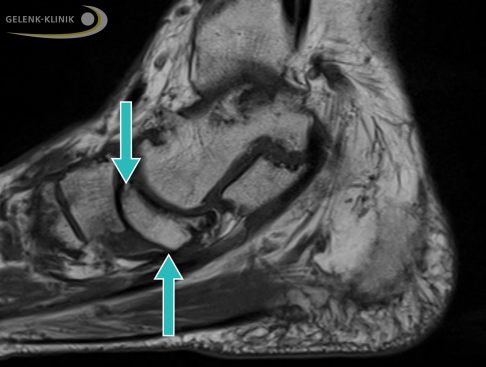

Eine frühe Diagnose ermöglicht dem Spezialisten die Magnetresonanztomographie (MRT). Durch die MRT kann der Spezialist bereits ein Knochenödem im betroffenen Kahnbein nachweisen. Er wird dann weitere bildgebende Untersuchungen wie Röntgen oder digitale Volumentomographie (DVT) unter Belastung und schräge bzw. seitliche Aufnahmen veranlassen.

Magnetresonanztomographie (MRT) bei Müller-Weiss-Syndrom: Das defekte Kahnbeinfragment sinkt im Fuß nach unten ab (Pfeile). Es verdrängt und komprimiert die darunter liegenden Weichteile. © Gelenk-Klinik